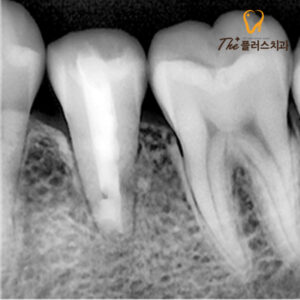

환자분의 정확한 상태를 알아보기 위해

먼저 X-ray 촬영을 진행하였는데요.

정상적으로 닫혀있는 치근의 모양이 아닌

근관이 열려있는 형태의

기형치로 염증이 발생해 있었습니다.